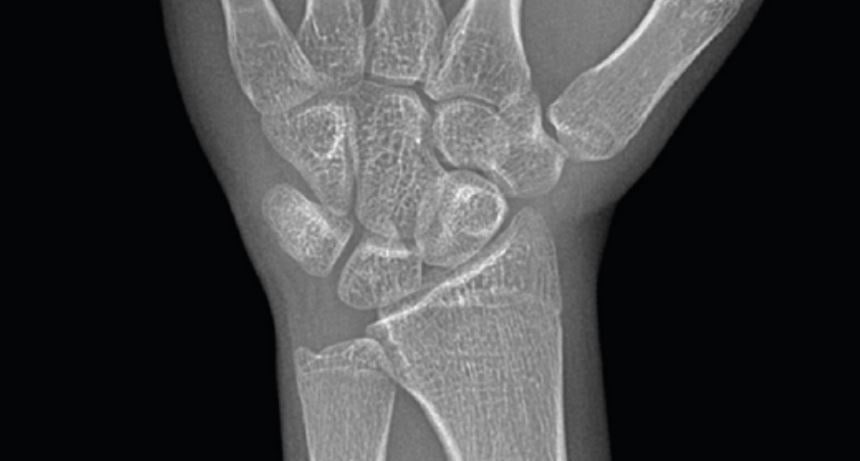

![연세굿데이치과] 성장판 검사가 중요한 이유 관련 이미지 7](https://pub-9f2bb3498faf4d1d8714b41df24753e3.r2.dev/content/clinics/archive/5hurea2jnb/naver_blog/eunkyo3370/assets/by_hash/a7bbb9c6eaa0c53b35b9bfc01f4f48437c999d46f7dff0a1c54a2bb8a3e8098a.jpg)

![연세굿데이치과] 성장판 검사가 중요한 이유 관련 이미지 8](https://pub-9f2bb3498faf4d1d8714b41df24753e3.r2.dev/content/clinics/archive/5hurea2jnb/naver_blog/eunkyo3370/assets/by_hash/22108e17ead5bf4fe4b4ccdebf634e1c1ea8c46ba988a0bc9fd54ac54e727e1f.jpg)

![연세굿데이치과] 성장판 검사가 중요한 이유 관련 이미지 9](https://pub-9f2bb3498faf4d1d8714b41df24753e3.r2.dev/content/clinics/archive/5hurea2jnb/naver_blog/eunkyo3370/assets/by_hash/f3d84a710e8ec881ebccef853121a8d661ddbe7e64954f334aa64a9f93f70e00.jpg)

(실제 연세굿데이치과가 제공해드리는 성장검사 분석결과지)

연세굿데이치과는 성장판 검사후

아이의 키가 얼마나 자랄지,

가장 좋은 교정시기는 언제인지 확인할 수 있는

성장보고서를 함께 제공해드립니다.